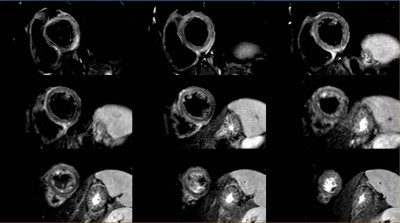

Myokarditis - Was ist mit meinen Ferkeln los? - Klinische Fälle - 3drei3 ... / Ein mikroskopbild der myokarditis bei der autopsie bei einer person mit akutem auftreten von herzinsuffizienz.

Et mikroskopbillede af myokarditis ved obduktion hos en person med akut debut af hjertesvigt. Myokarditis bedeutet entzündung der herzmuskulatur. Sie führt zu einer abnahme der leistungsfähigkeit des herzens (herzinsuffizienz) und zu herzrhythmusstörungen. Learn vocabulary, terms and more with flashcards, games and other study tools. Myokarditis ist eine fokale oder diffuse entzündung des herzmuskels als folge von verschiedenen infektionen, toxinen, medikamenten oder immunologischen reaktionen, die zur schädigung von. Als myokarditis wird eine reihe entzündlicher herzmuskelerkrankungen unterschiedlicher ursache bezeichnet. Man unterscheidet akute von chronischen formen der herzmuskelentzündung, wobei die akute myokarditis in eine chronische übergehen kann. Myokarditis oder pankarditis läuft ein akuter oder chronischer.

Ein mikroskopbild der myokarditis bei der autopsie bei einer person mit akutem auftreten von herzinsuffizienz.